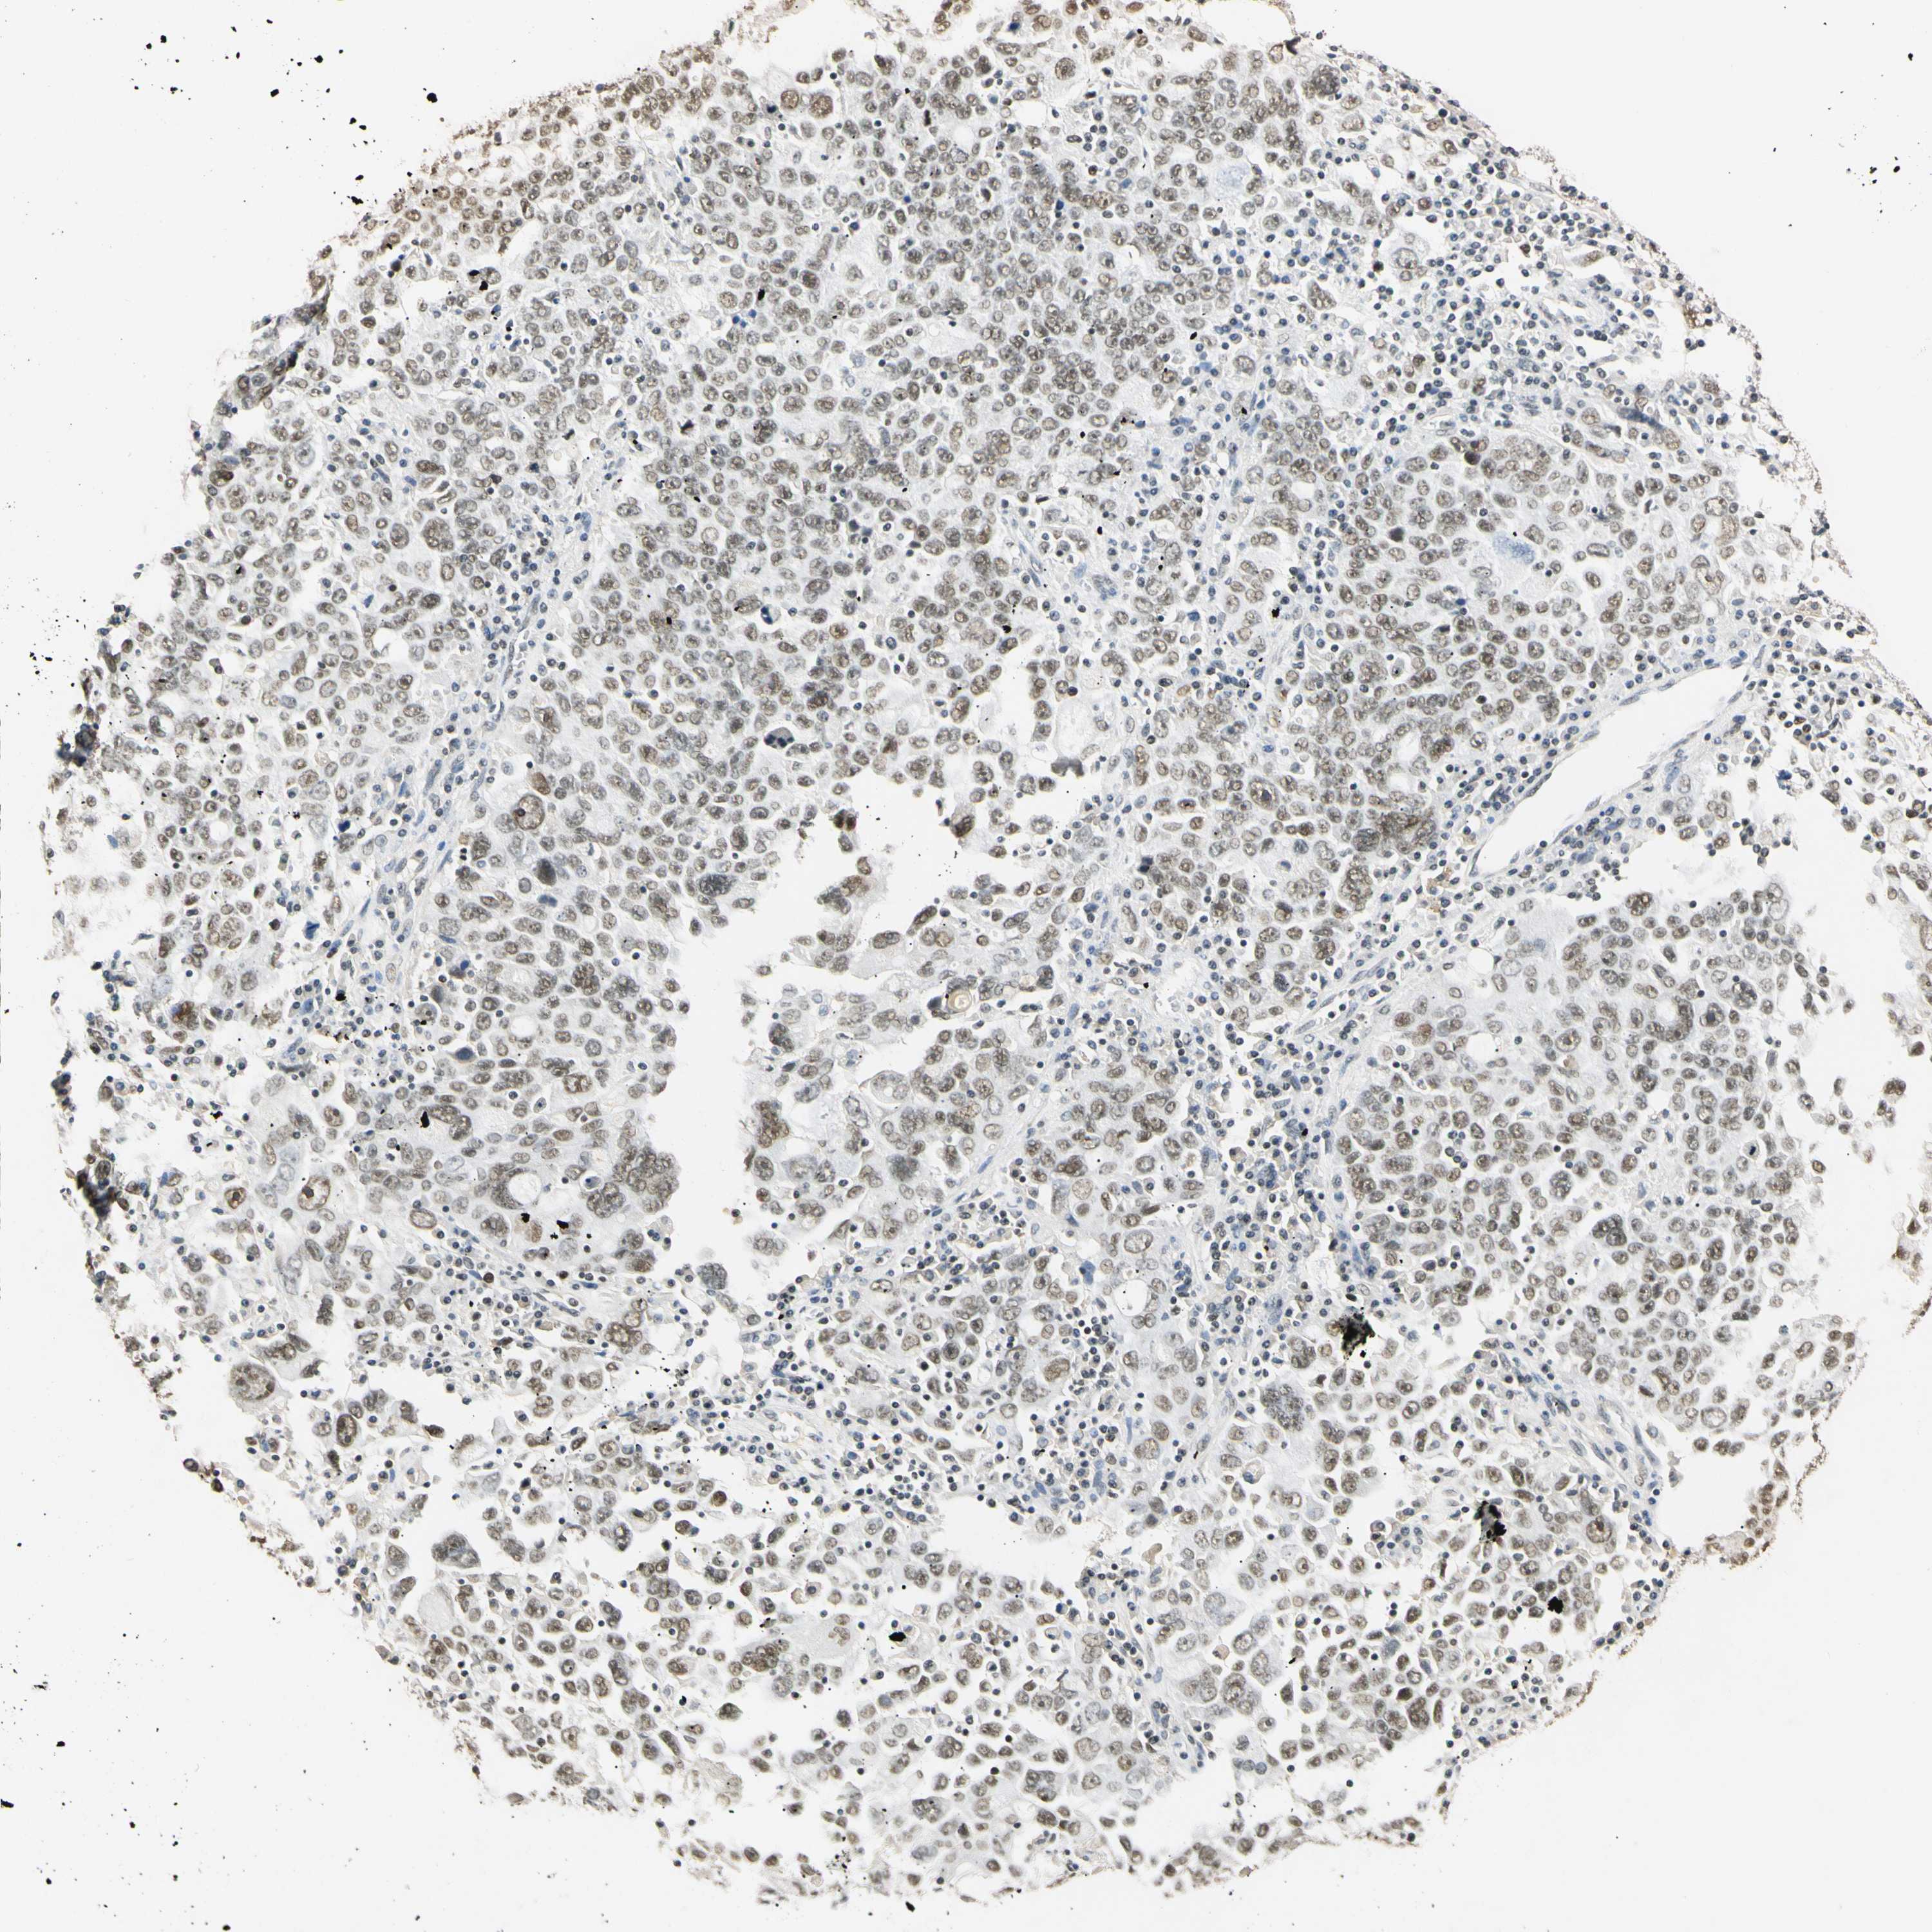

OVARIAN CANCER - Protein expressioni

A mouse-over function shows sample information and annotation data. Click on an image to view it in a full screen mode. Samples can be filtered based on level of antibody staining by selecting one or several of the following categories: high, medium, low and not detected. The assay and annotation is described here.

Note that samples used for immunohistochemistry by the Human Protein Atlas do not correspond to samples in the TCGA dataset.

Antibody stainingi

Antibody staining in the annotated cell types in the current human tissue is reported as not detected, low, medium, or high, based on conventional immunohistochemistry profiling in selected tissues. This score is based on the combination of the staining intensity and fraction of stained cells.

Each image is clickable and will lead to virtual microscopy that enables deeper exploration of all samples and also displays staining intensity scores, fraction scores and subcellular localization as well as patient and tissue information for each sample.

Antibody HPA008751

Antibody CAB005227

Cystadenocarcinoma, serous, NOS